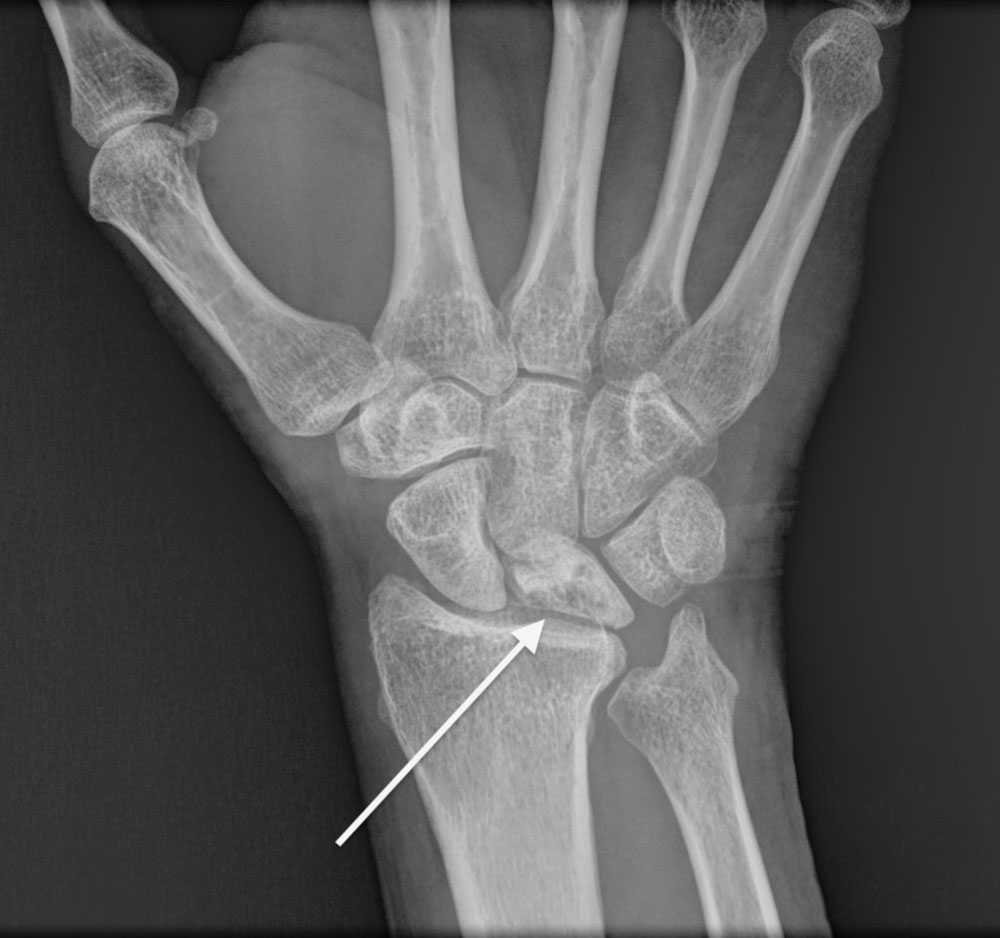

La enfermedad de Kienböck, también conocida como necrosis avascular del hueso semilunar, es una afección en la cual el hueso semilunar, uno de los ocho huesos pequeños en la muñeca, pierde el suministro de sangre que conduce a la necrosis (muerte) del hueso. El semilunar es un hueso localizado en el centro de la muñeca y es importante para el movimiento adecuado y el soporte de la articulación (Figura 1).  Realiza su función en estrecho contacto con los dos huesos del antebrazo (radio y cúbito) para ayudar a que la muñeca se mueva.

Figura 1 - Hueso semilunar en la muñeca.